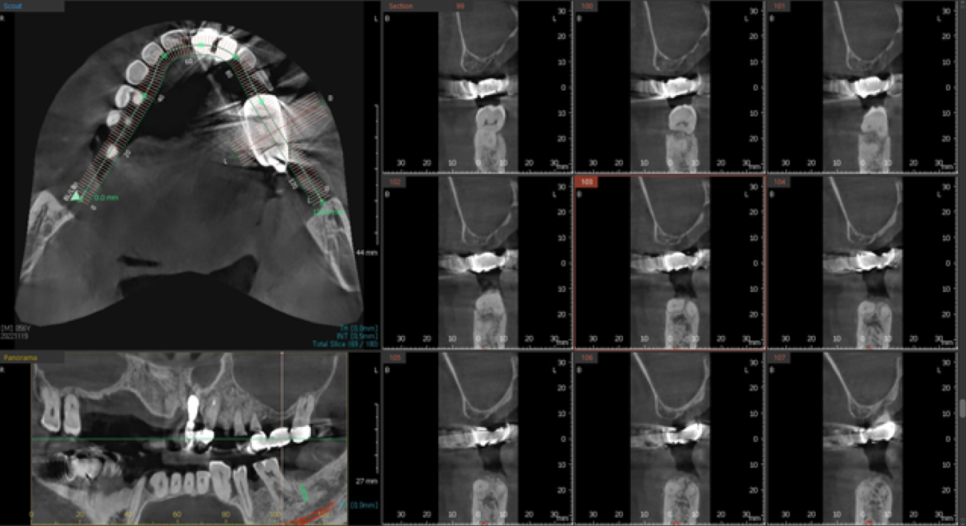

앞니 수술을 하기 위해서 3차원 CT 엑스레이 촬영을 했습니다.

CT 사진을 보며 적당한 위치를 선정하고, 임플란트의 길이와 두께를 정합니다.

뼈이식을 추가로 진행하였으며, 3개월 후에 보철을 올리기로 했습니다.

어느정도 치유가 되었기에 3차원 CT 촬영 후, 왼쪽아래 큰어금니 임플란트 수술을 진행하도록 합니다.

앞뒤 인접치의 관계도 고려하고,

3차원 CT로 봤을 때, 뼈가 더 많이 차있는 안정적인 위치를 선택합니다.

신중하게 위치를 선택하기 위해 파노라마 엑스레이를 중간에 촬영했습니다.

3차원 CT상에서도, 파노라마 엑스레이도, 그리고 육안으로 봤을 때에도 좋습니다.

정확히 맞는 임플란트 길이와 직경을 선택하여 임플란트를 식립합니다.